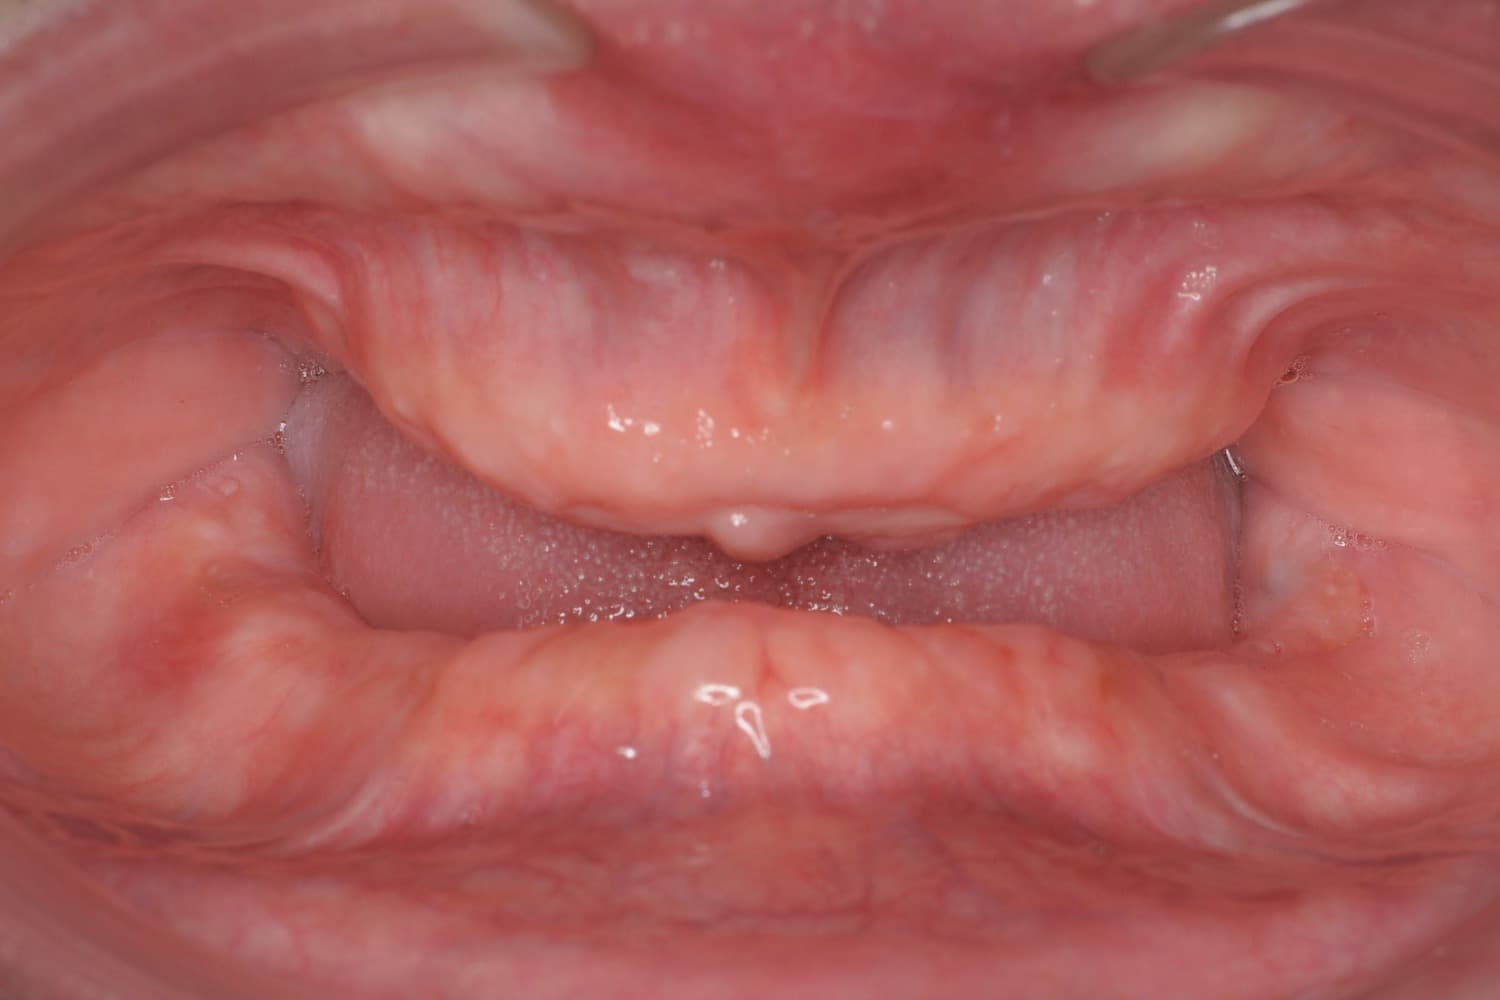

全歯のインプラント治療(50代/男性)

Before

オールオン4

年齢

50代

性別

男性

主訴

他院で総義歯を入れたが、噛むと上の義歯が落ちて使えない。インプラント相談希望。

治療期間

10カ月

治療回数

12回

費用

6,000,000円+骨造成代

副作用・リスク

メインテナンスが出来ていないとインプラント周囲炎になる。よく噛めるため、上部構造が使用していくうちに破損することがある。